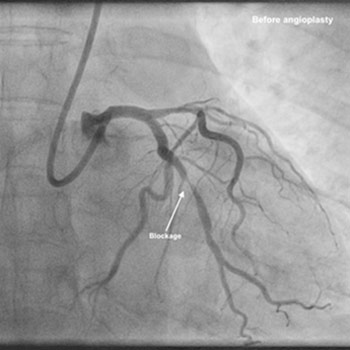

Triple vessel angioplasty (stenting) via radial approach (wrist).

This lady was seen in clinic with history of chest pain and found to have Treadmill test (TMT) +ve in Aug 2015. She was reviewed by our team and advised coronary angiography, but she didn’t turn up. After 2 months she came to see me again in OPD. In between, she had undergone angiogram in another hospital in the city, as someone known to her recommended that. After the angiogram, she was advised that she has block in 2 arteries and advised 2-vessel angioplasty. The family took the report and the CD to one another hospital in the city. They were told there were blockages in all 3 arteries and advised either angioplasty or bypass surgery (CABG). She and the family got confused with this and decided to come and see me. I reviewed the angiogram and explained to them about the problem- all 3 vessels had blockages, but all blockages are focal- which essentially means no need for long stents. After informed consent, we performed 3-vessel angioplasty through the wrist and inserted 3 stents successfully. She was discharged home in 2 days and been under my follow up since then. It is now more than 4 years and she is doing remarkably well with regular exercise and no symptoms. She has also travelled to Saudi Arabia to see her son for few months and been back.